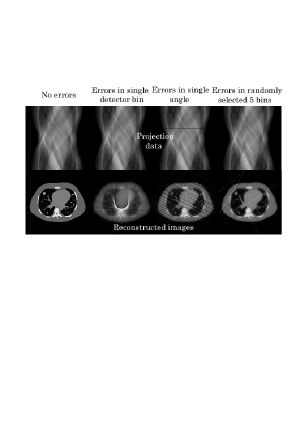

where denotes measurement noise. In ordinary iterative reconstructions, the cost function is designed by assuming that the noise component follows independent Gaussian distribution or independent Poisson distribution. On the other hand, in this paper, we consider the Abnormal Error Noise (AEN) model, in which most elements of are zeros but only a small number of elements of take non-zero abnormal error values occurred by various physical reasons described in Section 1. We assume that the abnormal projection data takes a value over the pre-specified interval with a uniform probability, where are pre-specified constants corresponding to the dynamic range to control error severity. To demonstrate that the abnormal errors in only a small number of projection data bins lead to significant artifacts, in Fig. 1, we show examples of reconstructed images for three typical cases, i.e. data corresponding to one detector element contains the error, data corresponding to one projection angle contains the error, and randomly selected five projection data bins contain the error. Furthermore, we also assume that locations of the abnormal data bins are unknown. Below, we explain that such noise model can be well represented by using a particular case of generalized Gaussian probability density function. In the generalized Gaussian model, the likelihood function of given is expressed as

We show reconstructed images together with the degraded projection data for all the scenarios in Figs. 3-5. In all the scenarios, the images by the -norm reconstruction were severely damaged by the abnormal errors, in which the artifact patterns, i.e. streaks, random errors, etc., depend on the locations of abnormal bins. The empirical projection space median filtering succeeded in reducing the artifacts, but the filtering also affects the correct data so that we can observe some additional artifacts in the final images. On the other hand, for the cases of Detector Error 1, Angle Error 1, and Random Error 1 with relatively mild errors, the power of identifying the abnormal bins in both the -norm and -TV reconstructions were significant in which they succeeded in reconstructing almost perfect images. However, the difference between the -norm reconstruction and the -TV reconstruction became apparent for the more difficult cases of Detector Error 2, Angle Error 2, and Random Error 2. In these cases, the -TV reconstruction correctly identified most of the abnormal bins whereas the -norm reconstruction did not succeed perfectly. With respect to convergence speed of the -norm and -TV reconstructions, they were a bit slower compared with the -norm reconstruction and the standard ART algorithm mainly because early iterations need to be spent to correctly identify the locations of abnormal bins. However, thanks to their row-action structures, they seem to be still significantly faster than using the standard -norm and -TV minimization algorithms (for example, popular iterative reweighted least-squares method [3],[4]) which can be used for the same cost functions.